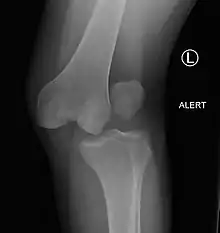

![]() | |

| Plain lateral X-ray of the left knee showing a posterior knee dislocation[1] | |

Plain X-rays, CT scan, ultrasonography, or MRI may help with the diagnosis.[2][11] Findings on X-ray that may be useful among those who have already reduced include a variable joint space, subluxation of the joint, or a Segond fracture.[5]

They may be divided into five types: anterior, posterior, lateral, medial, and rotatory.[4] This classification is based on the movement of the tibia with respect to the femur.[11] Anterior dislocations, followed by posterior, are the most common.[2] They may also be classified on the basis of which ligaments are injured.[2]